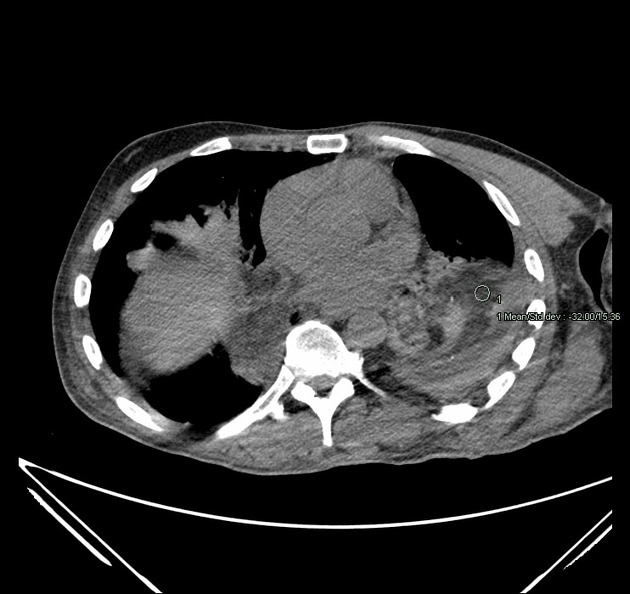

What are the causes of lipoid pneumonia?

a) Exogenous- aspiration of oil

b) Endogenous- more common- secondary to post obstructive processes ie Fat density in consolidation